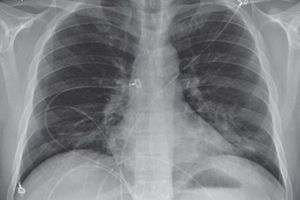

Trong việc chẩn đoán và điều trị người bệnh Covid-19, việc sử dụng hình chụp X-quang là phương pháp chẩn đoán hình ảnh dễ tiếp cận.

Công nghệ chụp cắt lớp vi tính (CT) hay X-quang có thể giúp các bác sĩ phân tích, tìm kiếm dấu vết của Covid-19 bằng hình ảnh.

Một số cuộc nghiên cứu ngay từ giai đoạn đầu của đại dịch cũng cho thấy trong hình ảnh chụp X-quang lồng ngực của bệnh nhân nhiễm virus có những điểm bất thường.

Trên cơ sở đó, Tổ chức Y tế Thế giới (WHO) đã khuyến nghị sử dụng công nghệ chụp X-quang để chẩn đoán bệnh nhân mắc Covid-19 khi chưa có điều kiện xét nghiệm rRT-PCR, đặc biệt đối với những bệnh nhân có triệu chứng nặng.Tuy nhiên, việc sử dụng công nghệ X-quang cũng cần đòi hỏi nguồn nhân lực y tế. Các bác sĩ chẩn đoán cần có chuyên môn, phân tích hình ảnh kỹ lưỡng bởi các dấu hiệu mắc Covid-19 thường khó phát hiện. Do đó, nhóm nghiên cứu đã phát triển một chương trình sử dụng trí tuệ nhân tạo để thực hiện việc chẩn đoán nhanh chóng hơn.